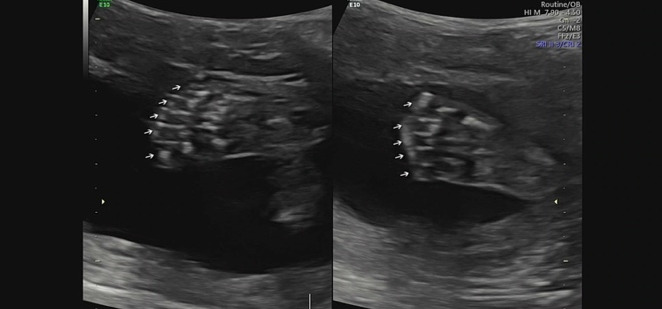

임신 20~22주에 시행하는 정밀 초음파는 아기의 머리부터 발끝까지, 탯줄과 태반까지 아이에게 구조적 이상이 있는지를 확인하는 검사다. 가장 중요한 기관들인 뇌, 심장, 위, 방광 등이 제대로 발달했는지, 사지가 다 붙어 있는지 일일이 확인한다. 손가락 발가락이 10개씩 다 있는지도 이때 확인할 수 있다. 그리고 주요 장기에 혈관들이 잘 연결되어 있는지도 확인하고, 주요 뼈 개수와 태반의 이상 유무, 그리고 구순구개열이 있는지, 귀가 잘 있는지 등을 확인한다.

KakaoTalk_20220916_204508933_01.jpg 우리 써니의 발, 발가락 10개 다 있어요!